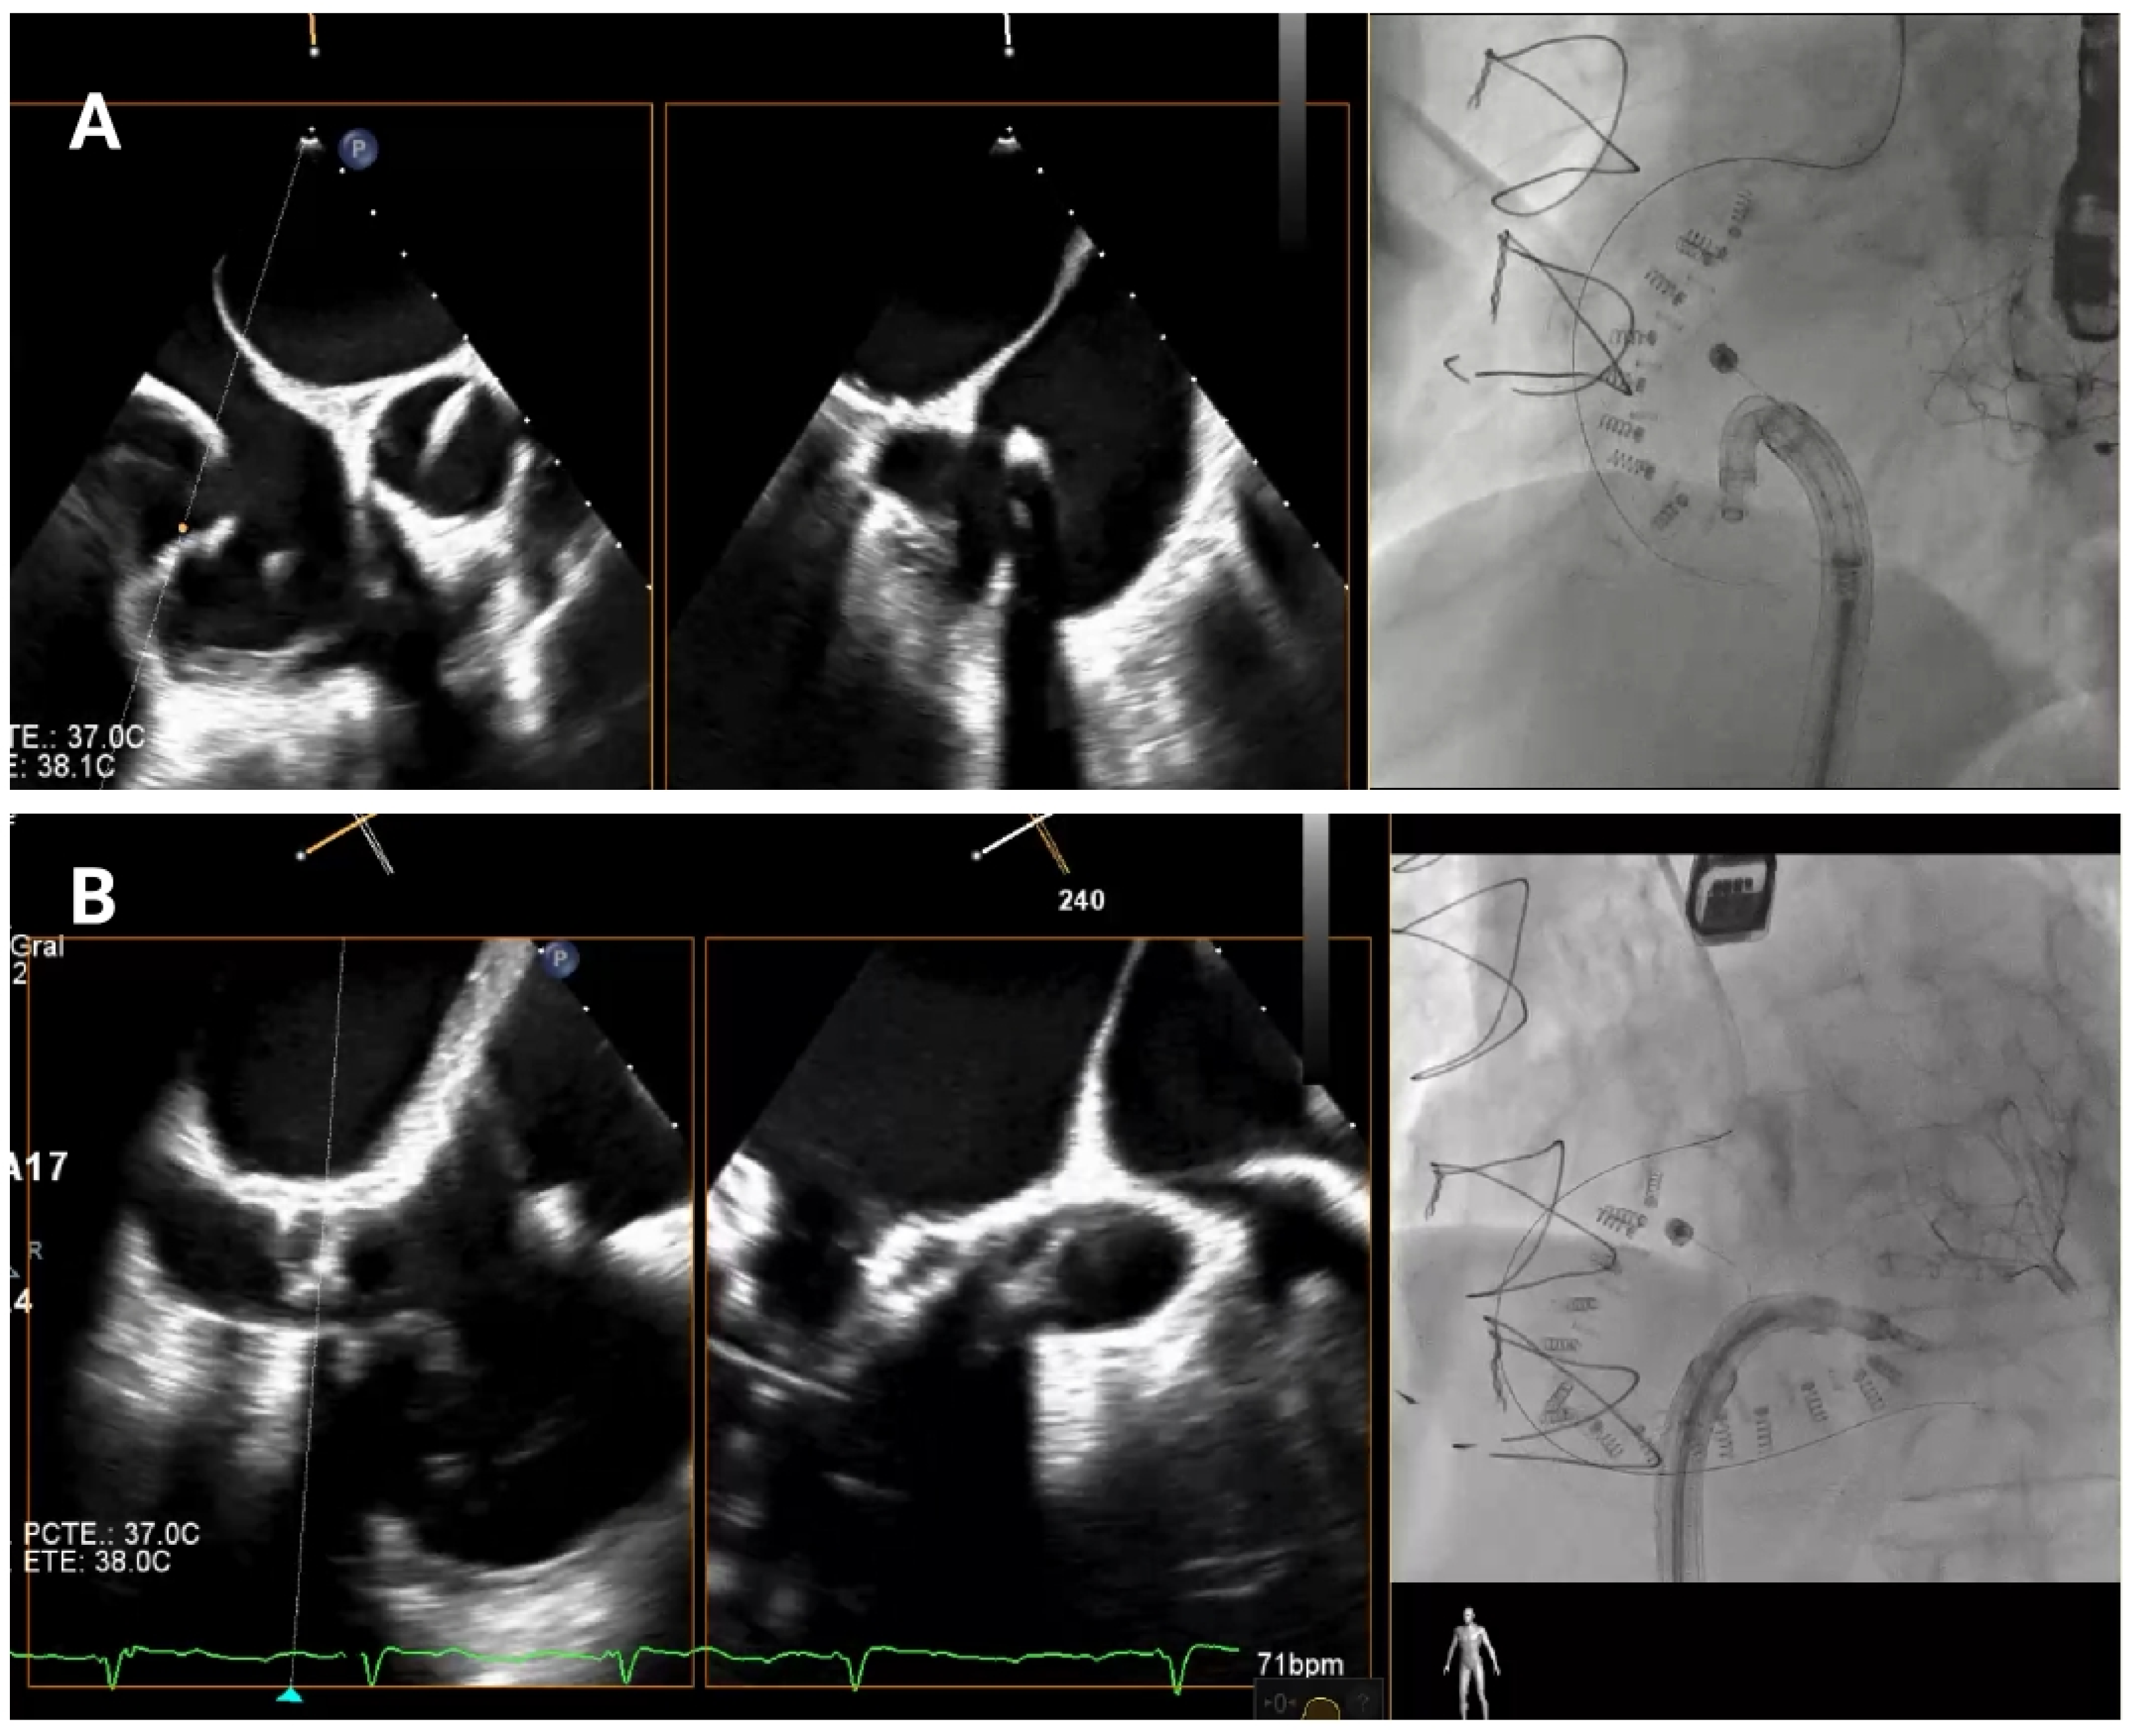

As the guide catheter approaches the tricuspid valve (

Figure 4), it is important to avoid structural interference or leaflet damage. Angiographically, the left anterior oblique projection helps visualize the anteroseptal commissure of the tricuspid annulus and ensures avoidance of the RCA course. Echocardiographically, transgastric views help visualize the anterior and posterior annulus, while high, mid, and deep esophageal views are useful for assessing the lateral annulus.

After the catheter is near the anteroseptal commissure, TEE and angiographic views are used together to check the IC tip alignment as it moves towards the tricuspid annulus. RAO projections allow visualization of the IC’s approach to the annulus with respect to its surrounding anatomy in order to confirm that the catheter’s tip follows the intended trajectory towards the target anchor points and is not obstructed by the leaflet or at risk of inducing injury. TEE bi-plane views are then employed to monitor precise positioning in relation to the hinge points and to ensure that the IC makes accurate contact with the annular tissue.

Any deviation from the hinge point region can compromise device efficacy, so continuous checks are essential to avoid positioning errors. If the IC alignment appears compromised at any stage, TEE enables quick reassessment to confirm or correct catheter orientation relative to the tricuspid valve.

Figure 4.

Delivery system navigation. The mid-esophageal bicaval view supports real-time visualization of the steerable sheath and guide catheter, while the mid-esophageal short-axis view aids in assessing the distance to the aorta. As the guide catheter nears the tricuspid valve, fluoroscopic left anterior oblique projection helps identifying the anteroseptal commissure and avoiding the right coronary artery.